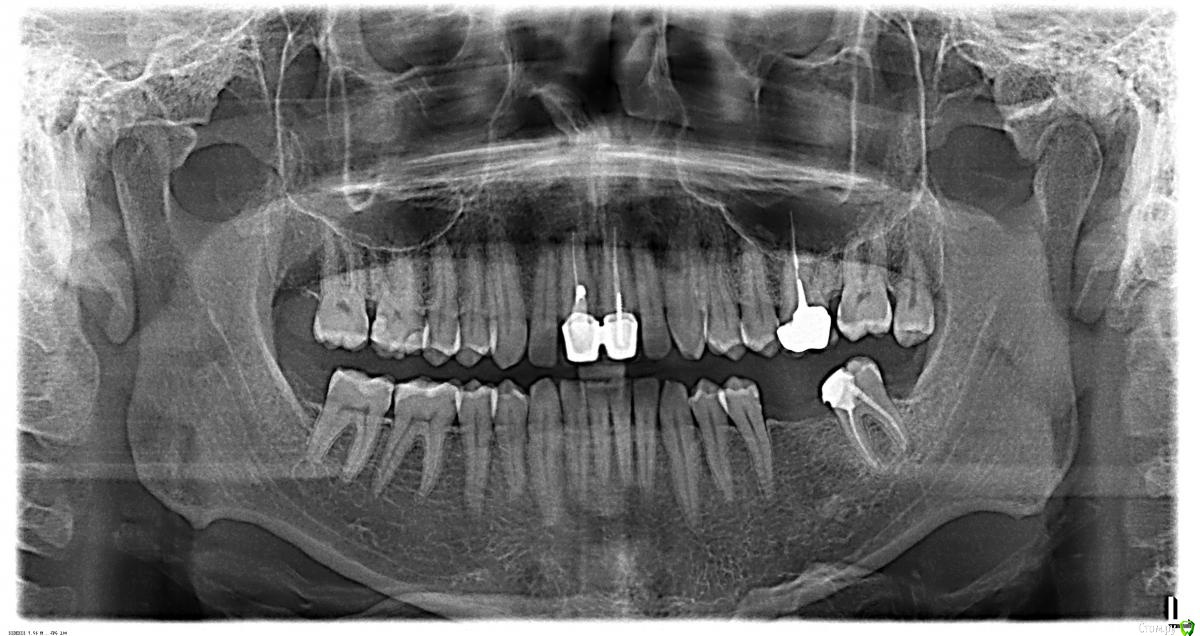

Dmitriy_ Опубликовано 26 июля, 2016 Поделиться Опубликовано 26 июля, 2016 (изменено) Здравствуйте уважаемые доктора! Меня зовут Дмитрий, мне 36 лет. Вчера был на консультации по поводу установки имплантата на место левой 6-ки (зуба нет более 10 лет). Сразу скажу что место выбрал не очень удачно, был записан еще до того как нашел этот форум и решил все-таки сходить. На консультации сделали ОПТГ и несколько прицельных снимков разных зубов, тех что вызвали у них беспокойство.В итоге сказали что нужно сделать КТ, т.к. их очень беспокоит состояние зуба под коронкой, верхняя левая шестерка, возможно его придется удалить, а по этим снимкам непонятно. Вопросы:1. Действительно нужно сделать КТ или возможно какой-то другой снимок? Я недавно делал КТ области 5х5 где отсутствует 6-ка, его тоже посмотрели, но как я понял там этого зуба целиком не видно и фонит коронка. 2. Также сказали что эту коронку в любом случае нужно будет удалить, когда будут делать коронку на нижнюю 6-ку, т.к. она очень высокая и места внизу нет, по снимкам это наверное нельзя сказать, только очно? Спрашиваю, т.к. хочу сходить на консультацию по поводу имплантата еще в другую клинику, хочу прийти со всеми необходимым снимками, или хотя бы спросить делают ли они их. Спасибо!Если по остальным зубам что-то подскажете буду очень признателен. Изменено 26 июля, 2016 пользователем Dmitriy_ Ссылка на комментарий

St. Опубликовано 27 июля, 2016 Поделиться Опубликовано 27 июля, 2016 Добрый вечер! У Вас действительно есть несколько сомнительных зубов - шестой слева, о котором Вы говорили, и оба центральных резца верхней челюсти(особенно меня смущает правый).КТ лучше сделать, т.к. оно очень мжет помочь при принятии решения имеет ли смысл перелечивать каналы.Обратите внимание на зубы на предмет кариеса:вверху справа - 7 со стороны 6, 6 под пломбами с обоих сторон, вверху справа - 7 со стороны коронкивнизу слева - 5 со стороны отсутствующего зуба.Зуб мудрости вверху слева нужно удалить.Нижний 7 слева накрыть коронкой.Возможно во время очного осмотра найдутся ещё какие-то вопросы. 1 Ссылка на комментарий

Dmitriy_ Опубликовано 28 июля, 2016 Автор Поделиться Опубликовано 28 июля, 2016 (изменено) Добрый день! КТ лучше сделать, т.к. оно очень мжет помочь при принятии решения имеет ли смысл перелечивать каналы. Скажите пожалуйста, это касается только верхней 6-ки слева? Или резцов это тоже касается? В Пикассо (это сеть диагностических центров) можно нужную область на картинке выделить.Есть прицельный снимок резцов (прикладываю). Касательно резцов о чем идет речь, возможно даже удаление понадобится? Зуб мудрости вверху слева нужно удалить. Это сложное удаление? Т.е. нужно искать доктора для которого это рутина? Или терапевт который будет перелечивать зубки с этим справится? Зуб прорезался, смотрит в направлении щеки градусов на 40. Я щеткой еле достаю... St., спасибо большое за Ваш ответ! К модераторам: Я наверное ошибся разделом, в терапию нужно было? Изменено 28 июля, 2016 пользователем Dmitriy_ Ссылка на комментарий

St. Опубликовано 28 июля, 2016 Поделиться Опубликовано 28 июля, 2016 Скажите пожалуйста, это касается только верхней 6-ки слева? Или резцов это тоже касается? И тех, и других. Сегмент не получится сделать, т.к. зубы далеко и в один снимок не влезут. Тем более Вы ещё и имплантацию внизу планируете. Проще делать обе челюсти, чтоб было видно всё. Касательно резцов о чем идет речь, возможно даже удаление понадобится? Скорее всего нет. Вопрос в наличиии воспаления за пределами корня и необходимости перелечивания каналов. 1 Ссылка на комментарий